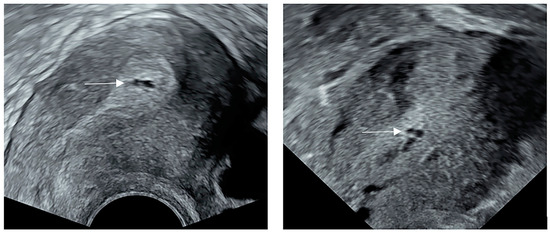

The Cystic Anechoic Zone of Uterine Cavity Newly Observed during Controlled Ovarian Hyperstimulation Affects Pregnancy Outcomes of Fresh Embryo Transfer

by Yizheng Tian, Shengrui Zhao, Jianan Lv, Hong Lv and Lei Yan

J. Clin. Med. 2023, 12(1), 134; https://doi.org/10.3390/jcm12010134 - 24 Dec 2022

During controlled ovarian hyperstimulation (COH), cystic anechoic zones in the uterine cavity are occasionally visible. This retrospective matched cohort study collected information on patients who underwent in vitro fertilization/intracytoplasmic injection (IVF/ICSI) from January 2014 to December 2020 at our center. The propensity score [...] Read more.

During controlled ovarian hyperstimulation (COH), cystic anechoic zones in the uterine cavity are occasionally visible. This retrospective matched cohort study collected information on patients who underwent in vitro fertilization/intracytoplasmic injection (IVF/ICSI) from January 2014 to December 2020 at our center. The propensity score algorithm matched 179 cases that had uterine cystic anechoic zones, with 358 which did not have uterine cystic anechoic zones cases. After matching, the live birth rate (38.0% vs. 48.6%, p = 0.025) of patients with uterine cystic anechoic zones was lower than that in the no uterine cystic anechoic zone group, while for clinical pregnancy miscarriage rate (22.2% vs. 12.4%, p = 0.031), the rate was higher. The results showed no correlation in the association between live birth rate (r = −0.027, p = 0.718), clinical pregnancy rate (r = −0.037, p = 0.620) or biochemical pregnancy rate (r = −0.015, p = 0.840) and the diameters of the cystic anechoic zones in the uterine cavity. There was a significant difference in the type of endometrium between the two groups (p < 0.001). The result of this study can provide guidance to patients on whether to undergo fresh embryo transfer in the current cycle. Full article